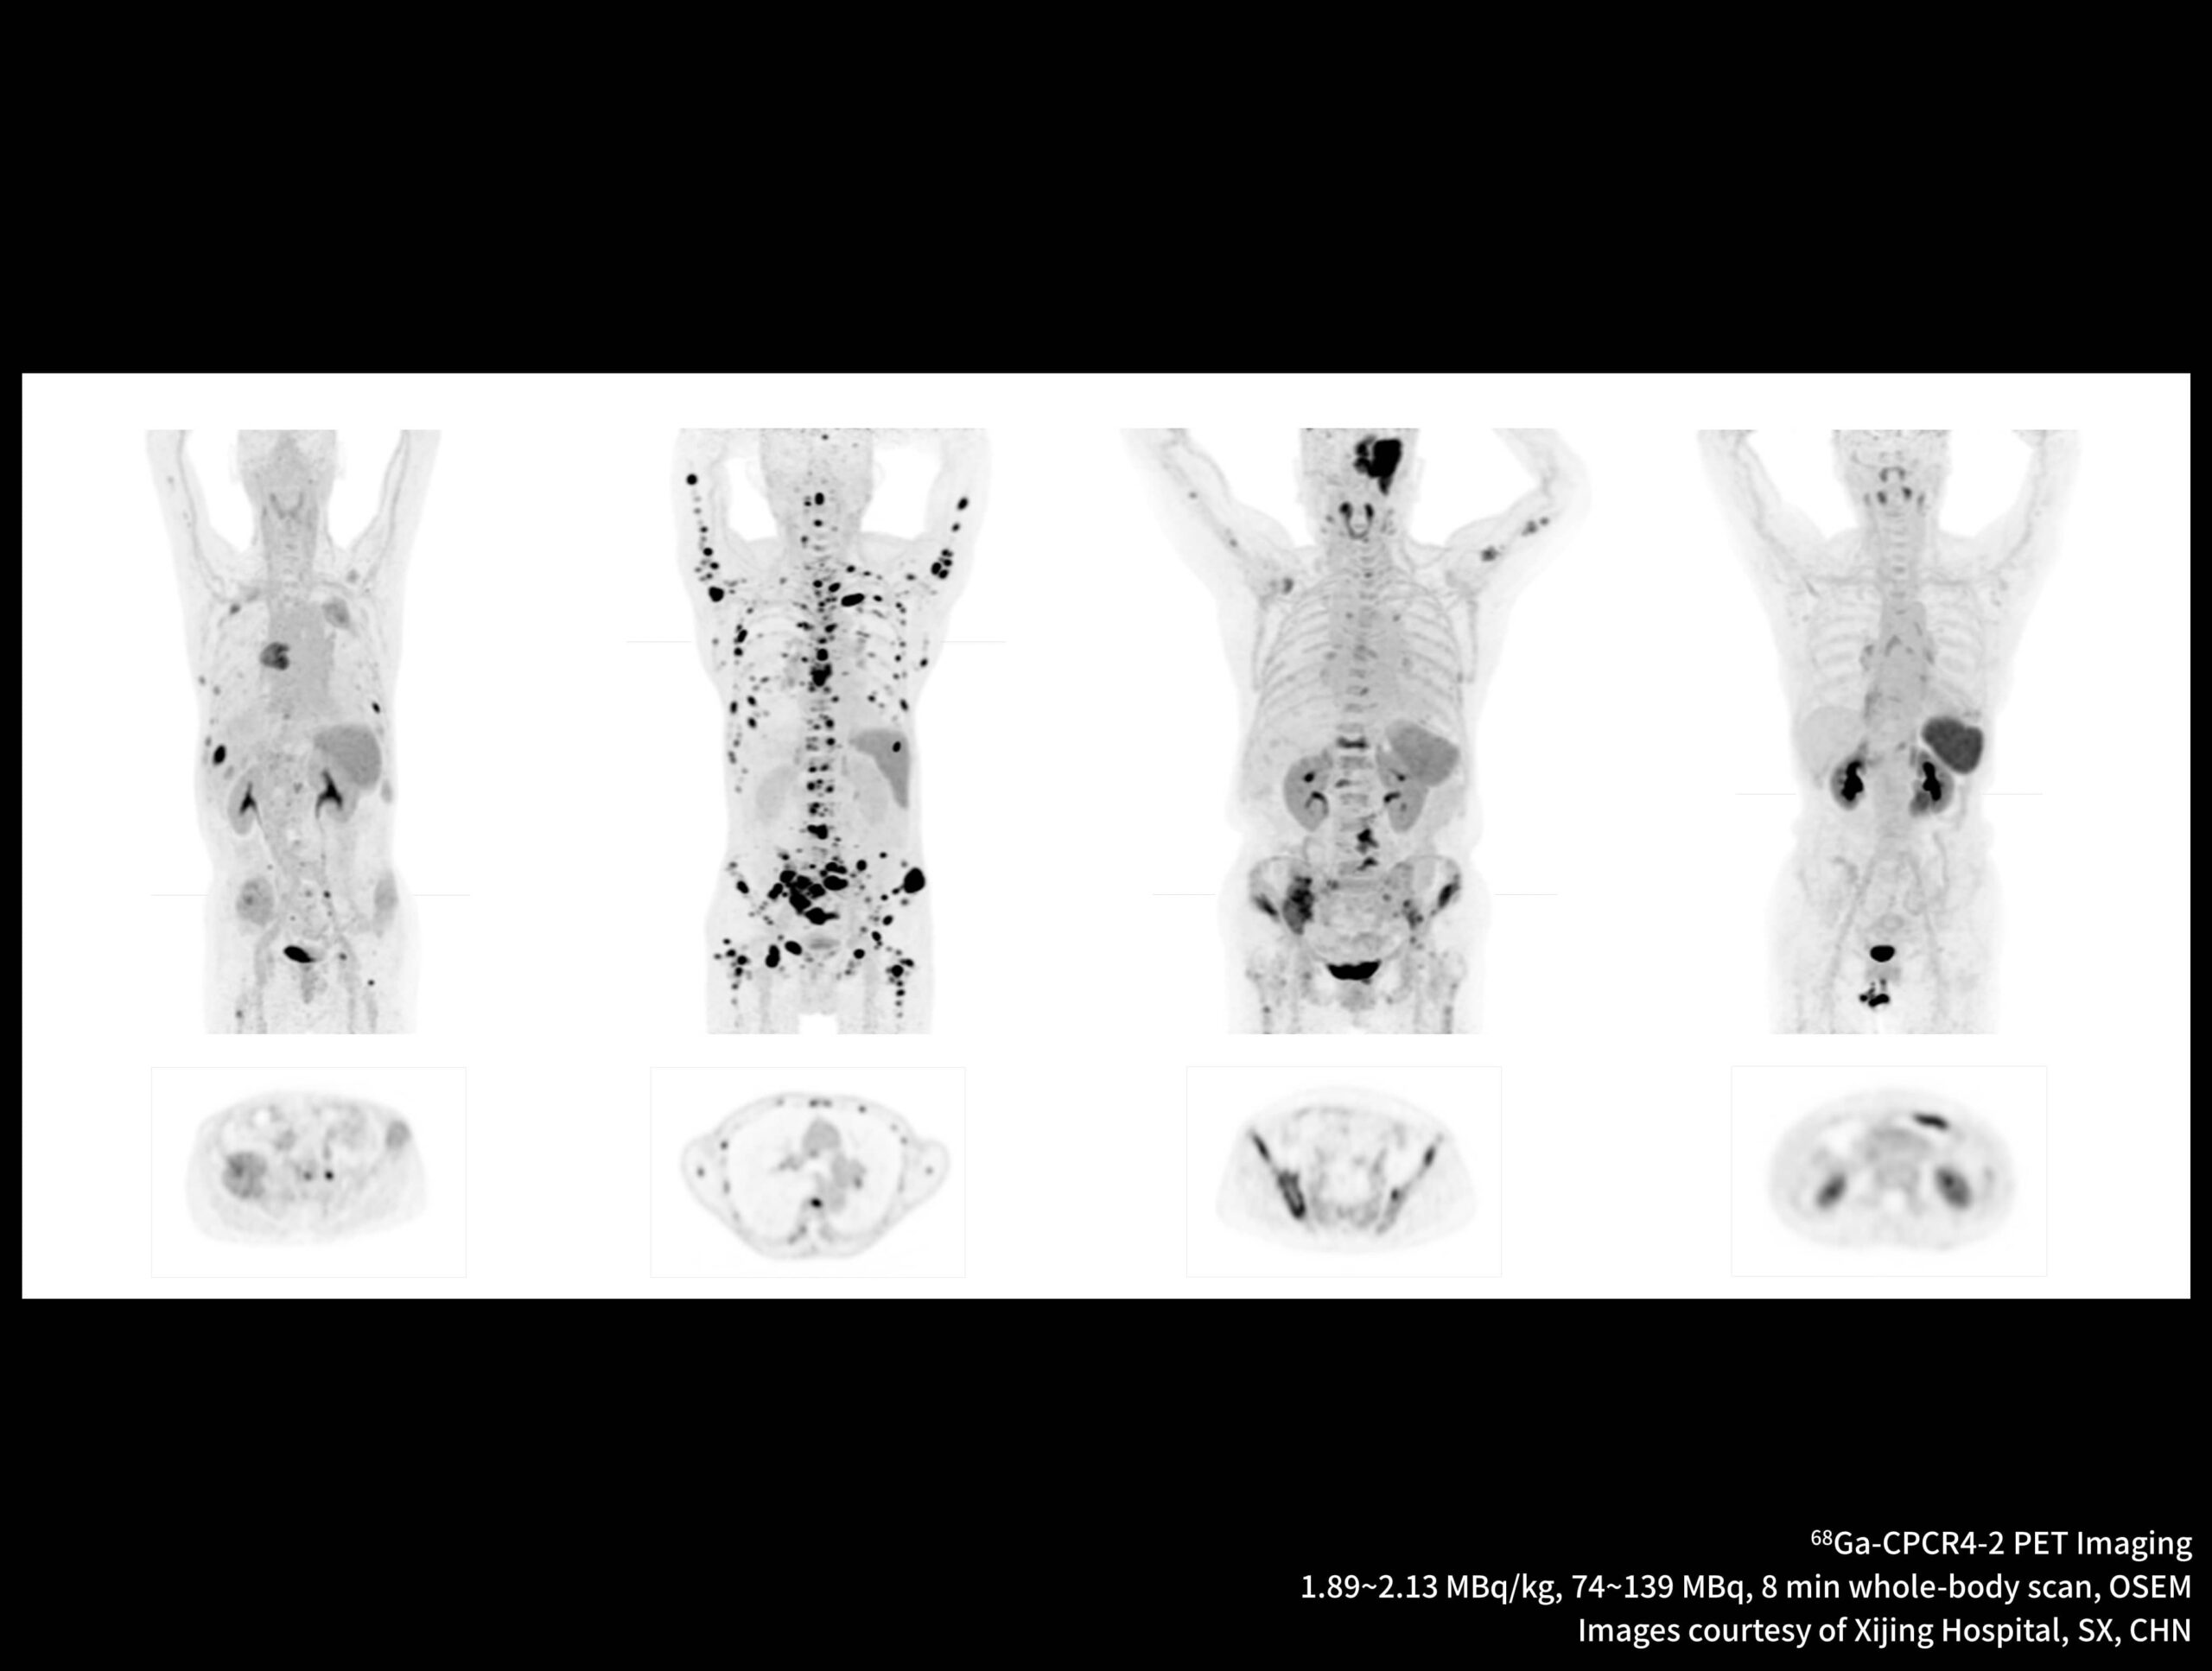

Imagistică PET/CT cu noi radiotrasori

Galerie de cazuri uMI Panorama